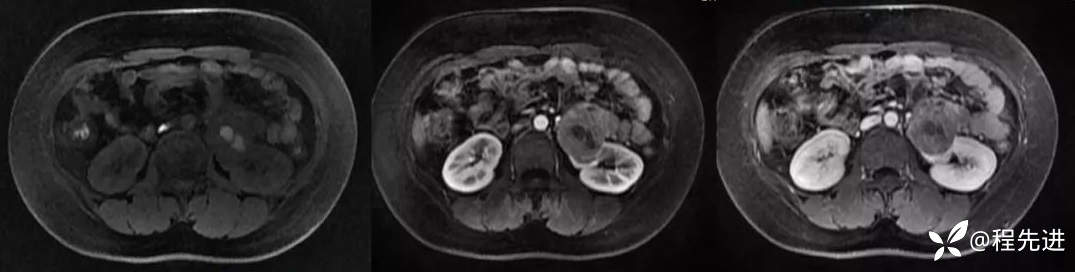

平扫,皮质期,髓质期: